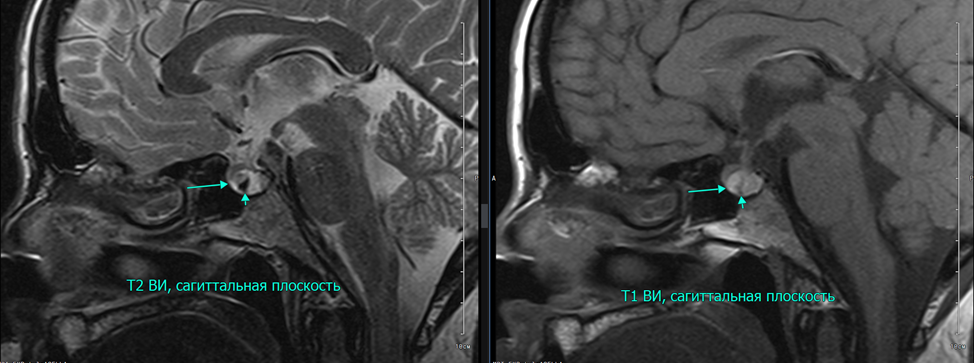

Рис. 5. На границе адено- и нейрогипофиза имеется мелкий очаг щелевидной формы, резко гипоинтенсивный на Т2, однородно гиперинтенсивный на Т1, размерами 1.1х0.3х0.7 см [стрелки].

Рис. 6. На границе между нейро- и аденогипофизом определяется жидкостное образование, округлой формы, гиперинтенсивное по Т2-ВИ, гипоинтенсивное по Т1-ВИ с четкими, ровными контурами, размером 0.55х0.4х0.3 см [стрелки].